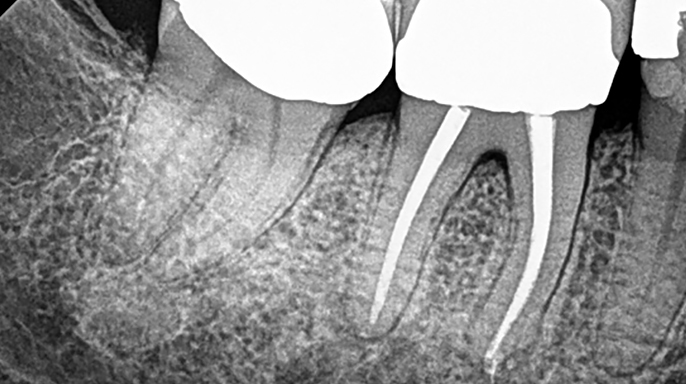

Co se stane, když ošetříte kořenový kanálek a léze se nehojí? Nejprve si musíte položit otázku: „Opravdu jsem úplně dezinfikoval zub? Našel jsem všechny kanálky a dostal jsem se na konec každého kanálku?“ Pamatujte, že milimetr je v endodontickém světě míle a pokud se nedostanete až k samotnému konci kanálku, stále zde mohou zůstat nějaké bakterie.

Nejprve tedy doporučuji skutečně posoudit váš dezinfekční protokol a mým návrhem bude vždy nejprve reendodoncie! Když zubaři často nedokážou vysvětlit, proč kořenový kanálek selhává, tak si automaticky myslí, že je zub prasklý, a začnou přemýšlet o nahrazení zubu. Ale to může být chybné! Nikdo není dokonalý a dokonce i ti nejlepší z nás musí provádět reendodoncie svých vlastních případů (zeptejte se mě, jak to vím!). Žádám vás tedy, abyste dali zubům šanci, a to obvykle znamená nejprve reendodoncii!

Pokud příznaky přetrvávají i po reendodoncii, přemýšlejte o dalších možnostech, jako je apexektomie. Existuje spousta anatomických studií, které ukazují, že v posledních 3 mm kořene mohou existovat rozsáhlé apikální ramifikace a isthmy. Pokud se tyto oblasti obtížně čistí, jedinou možností je fyzicky je odstranit apexektomií. Díky Bohu, že s tímto postupem přišli, protože nám umožňuje zachránit ještě více zubů.

Pamatujte, že apexektomie není něco, do čeho chcete jen tak skočit; chcete nejprve vyčerpat všechny své ortográdní možnosti. Při plánování léčby je třeba mít na paměti, že odstranění apexu ošetří pouze posledních 6 mm kořene, takže pokud máte podezření, že v celém kořeni jsou bakterie, musíte provést nejprve reendodontické ošetření. Vidíte, kam tím směřuji?